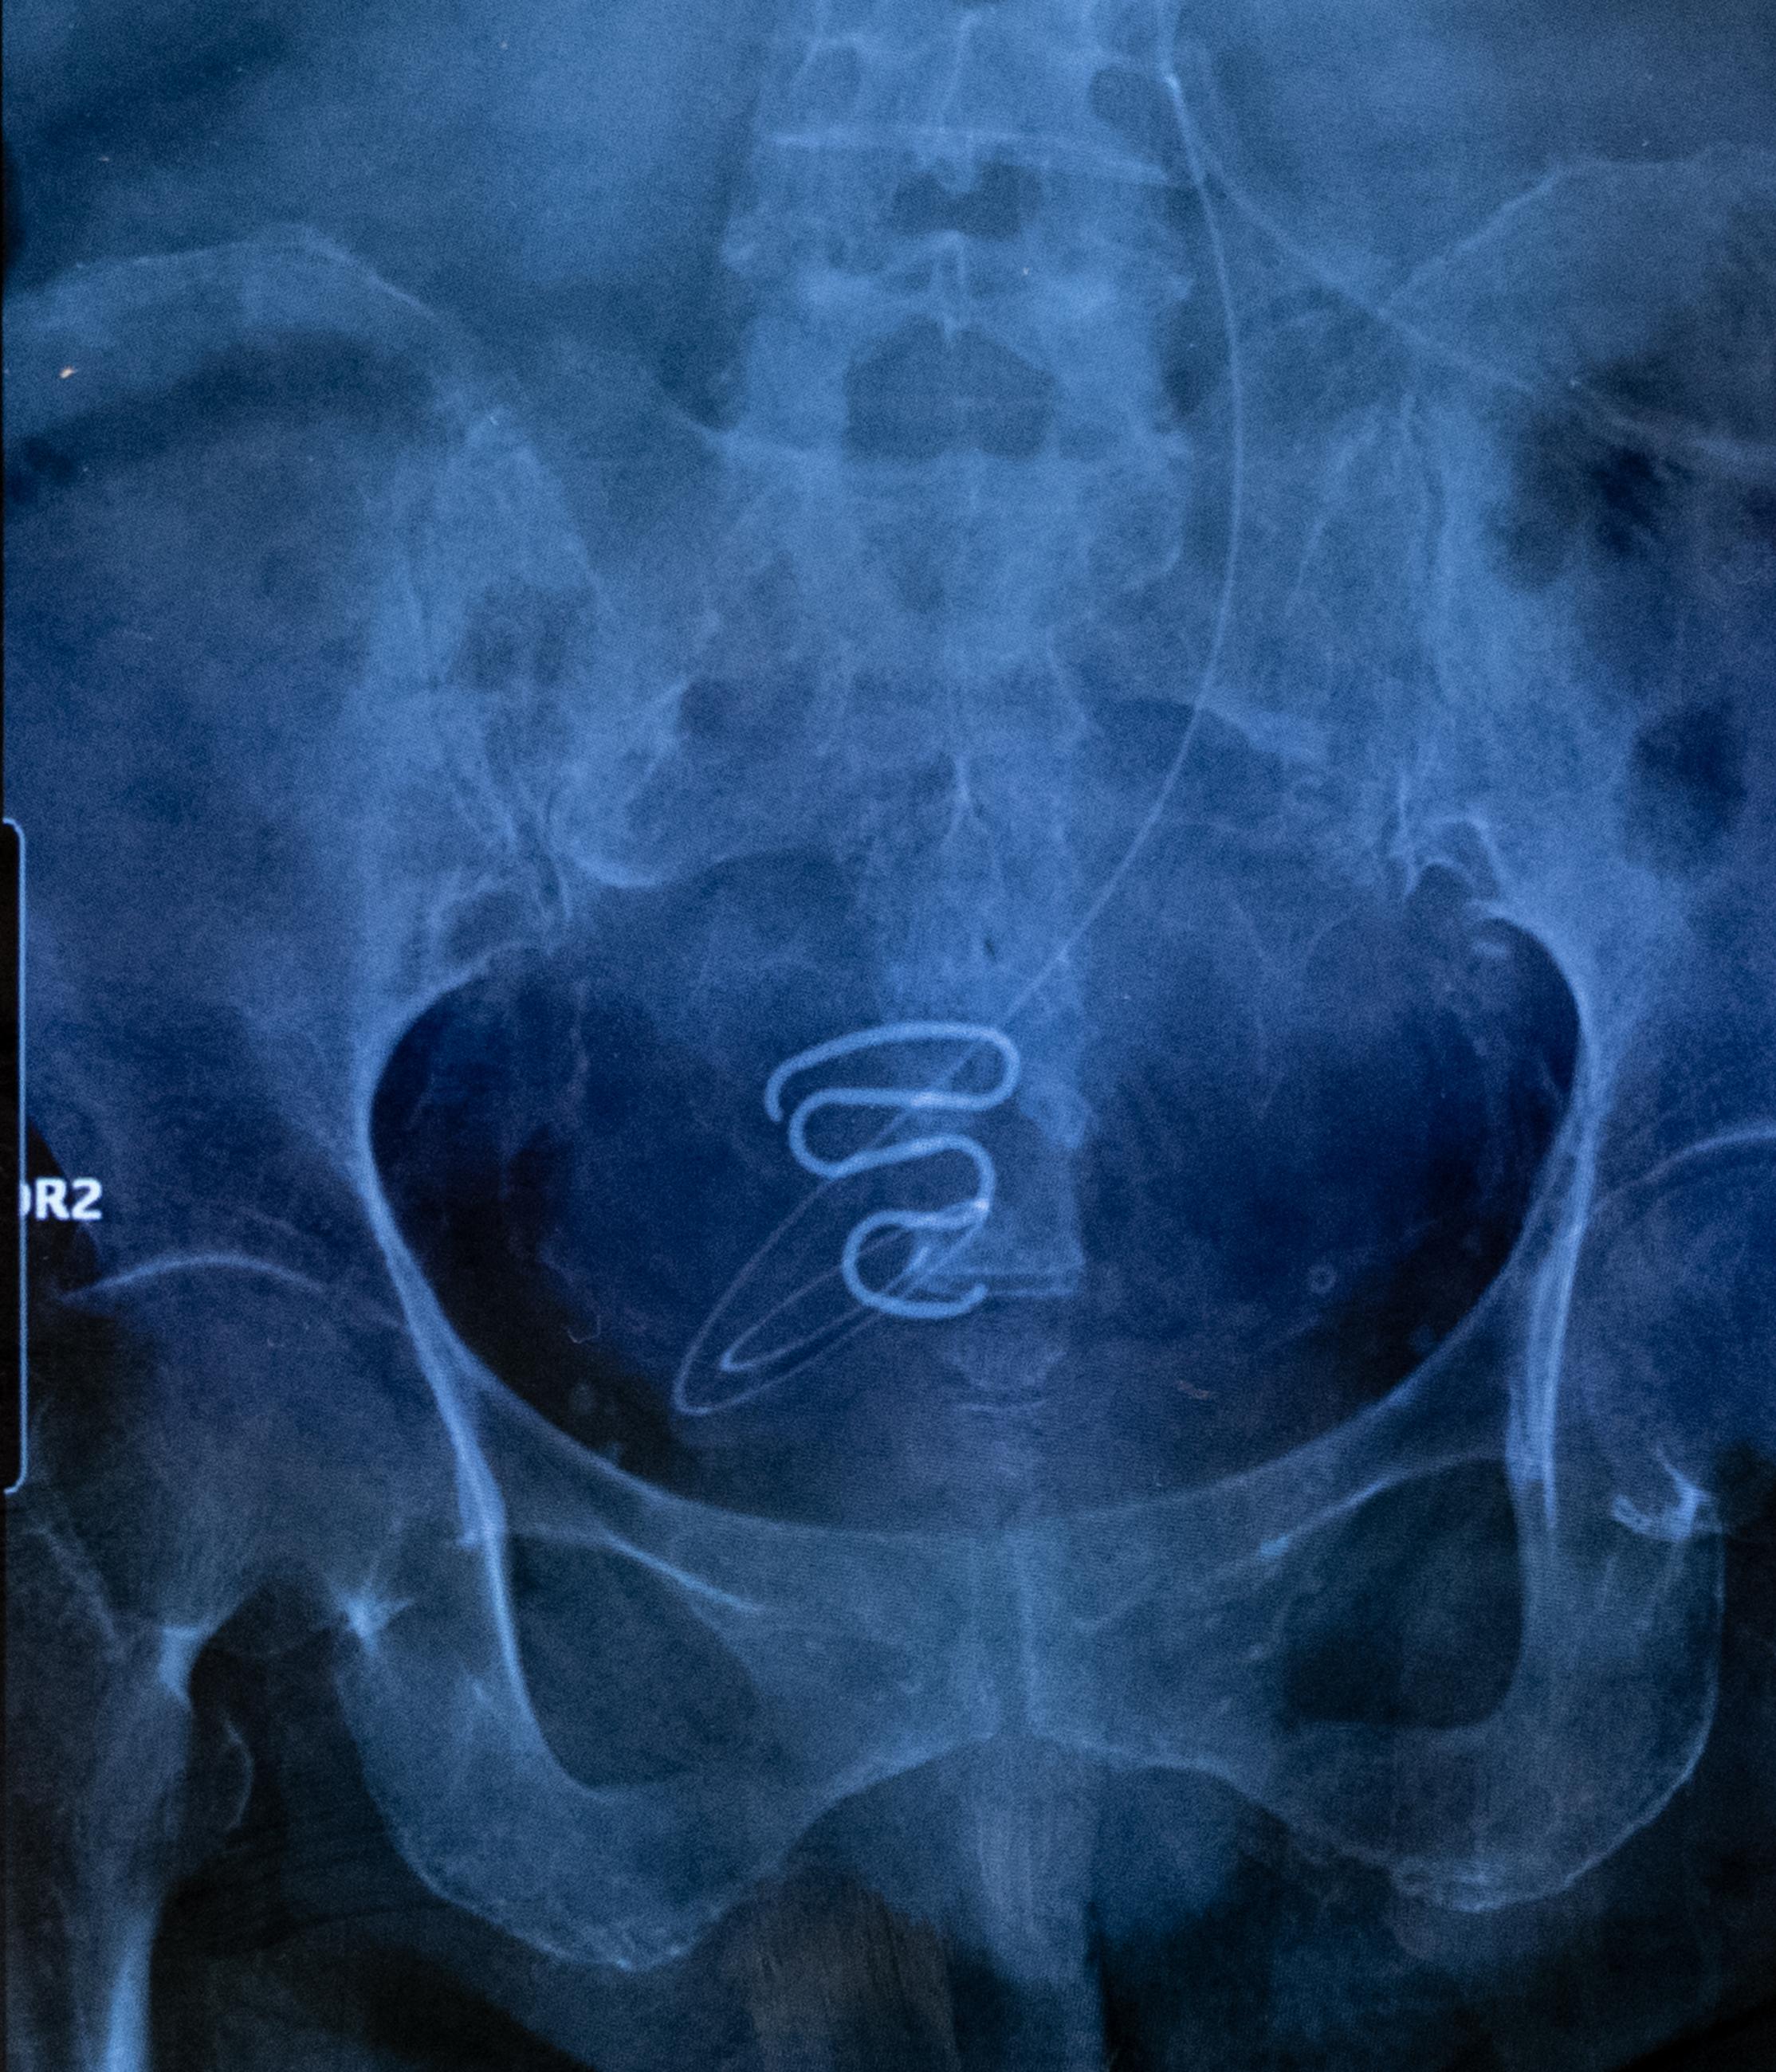

An X-ray showing an IUD – more commonly known as a ‘spiral’ – used during the Greenlandic forced contraception campaign (Spiralkampagnen) from 1966 to 1975. These IUDs were far too large and unsuitable for the bodies of young teenage girls, the youngest being only 12 years old at the time of insertion. In addition to the pain and bleeding, these ‘spirals’ sometimes caused serious infections that have made some victims permanently sterile.